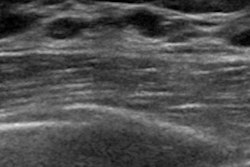

The Center for Diagnostics and Telemedicine of the Moscow Healthcare Department is highlighting a fetal phantom that aims to help sonographers-in-training. Image courtesy of the Center for Diagnostics and Telemedicine of the Moscow Health Department.